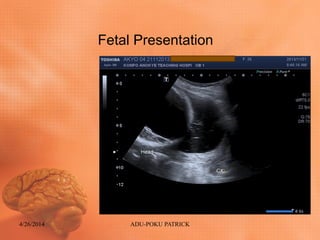

Ultrasound findings: FETAL

HEAD

• Intact skull

• Altered falx

• Extensive Intra cranial fluid collection with

little remnant of cortical mantle bilaterally

(residual brain tissue≥16mm)

• Fetus lie in cephalic presentation with fetal

head close to the maternal cervix.

Fetal Presentation